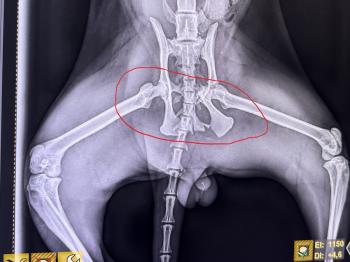

Die Untersuchungen bestätigten den ersten Verdacht: Castor war von einem Fahrzeug angefahren worden. Sein Körper trug Spuren seines harten Lebens – frische Wunden und alte Narben erzählten die Geschichte eines Straßenkämpfers, der trotz allem nicht aufgegeben hatte.

Doch damit nicht genug. Bei einem Krankheitstest wurde zudem festgestellt, dass Castor positiv auf Katzen-Immunschwäche (FIV) ist. Das schmälert natürlich seine Vermittlungschancen. Außerdem hat er eine komplizierten Beckenfraktur, die eine schwere Operation erforderlich macht. Glücklicherweise hat er Blase und Darm unter Kontrolle und ist in der Lage, die Katzentoilette zu benutzen.